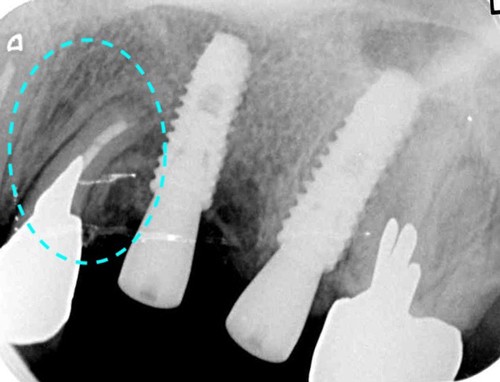

抜歯の結果、根は真っ二つ割れ、根の先端には大きな膿の腫瘍が骨を溶かしている良くない状態でした。